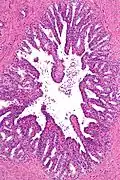

The inner lining of the seminal vesicles (the epithelium) is made of a lining of interspersed column-shaped and cube-shaped cells.[8] There are varying descriptions of the lining as being pseudostratified and consisting of column-shaped cells only.[9] When viewed under a microscope, the cells are seen to have large bubbles in their interior. This is because their interior, called cytoplasm, contains lipid droplets involved in secretion during ejaculation.[8] The tissue of the seminal vesicles is full of glands, spaced irregularly.[8] As well as glands, the seminal vesicles contain smooth muscle and connective tissue.[8] This fibrous and muscular tissue surrounds the glands, helping to expel their contents.[3] The outer surface of the glands is covered in peritoneum.[3]

Low magnification micrograph of seminal vesicle. H&E stain. -

High magnification micrograph of seminal vesicle. H&E stain.